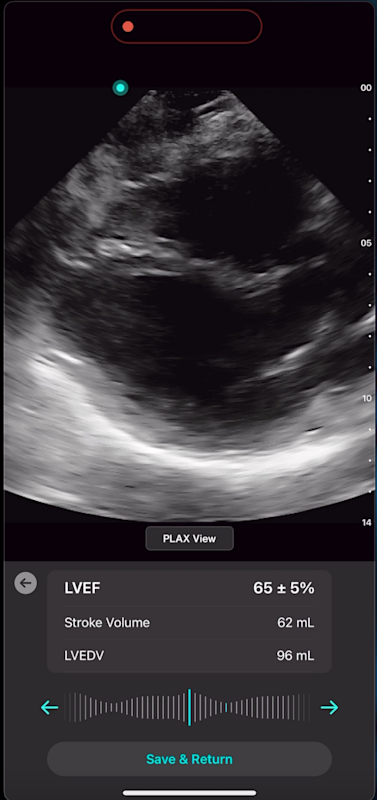

With Exo’s Cardiac AI, you can measure left ventricular ejection fraction (LVEF) and stroke volume in a few heartbeats in both parasternal long axis (PLAX) and apical four-chamber (A4C) views, making it easier than ever for POCUS users to get to answers.